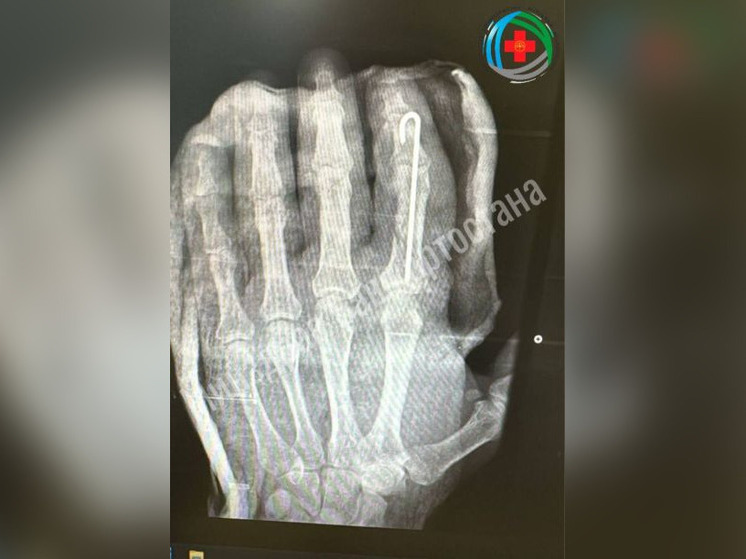

В Благовещенске врачи провели операцию по восстановлению ампутированного из-за травмы пальца.

Мужчина при работе с топором нанес неосторожный удар и лишился пальца. Врачи приняли решение провести экстренную операцию. Хирурги сшили мельчайшие сосуды, зафиксировали кости и провели реконструкцию мягких тканей.

Палец прижился, и пациент уже начал двигать им, проходя восстановительное лечение.